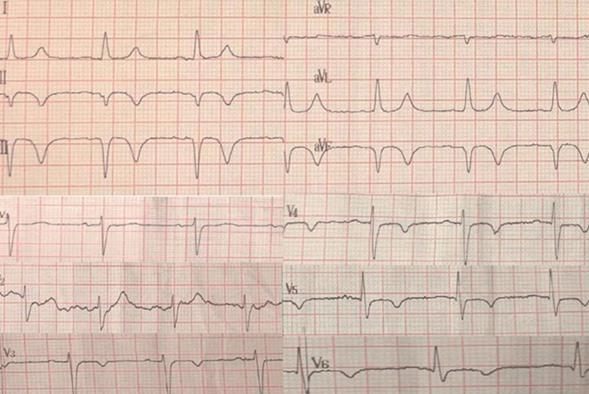

Historia de una semana de evolución de ángor a esfuerzos moderados, ante el cual no consulta. El 12/4/20 instala episodio de síncope, consultando en puerta de emergencia. Tomografía de cráneo sin alteraciones. Se otorga alta con control en policlínica, y realización de Holter que evidencia secuela inferior. Se contacta a la paciente el 17/4/20. A la llegada a urgencia, instala ángor de reposo con troponinas positivas inicialmente y en ascenso. El electrocardiograma evidencia imagen de infarto de pared inferior, evolucionado, con isquemia anterolateral extensa (figura 1). Se realiza ecocardiograma transtorácico (ETT) que muestra: ventrículo izquierdo (VI) con aquinesia ínferobasal, fracción de eyección del ventrículo izquierdo (FEVI) estimada en 55%.